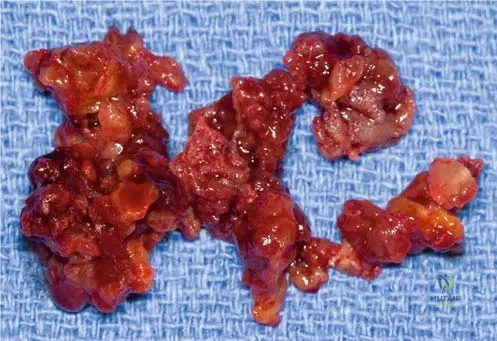

Question 24

View Answer & Explanation

Correct Answer: C

Rationale: Maffucci syndrome is characterized by the combination of multiple enchondromas (similar to Ollier's disease) and soft tissue hemangiomas or lymphangiomas. The bluish, compressible lesions and phleboliths are indicative of hemangiomas. Ollier's disease lacks the vascular lesions. Klippel-Trenaunay and Sturge-Weber syndromes are primarily vascular malformation syndromes with different skeletal involvement. Neurofibromatosis Type 1 has café-au-lait spots and neurofibromas, not enchondromas and hemangiomas.

Question 35